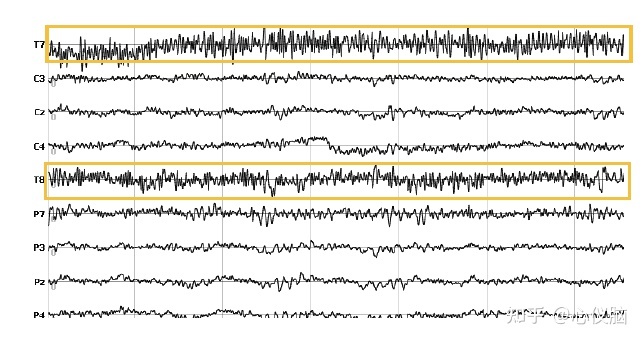

2.肌电伪迹

肌电由于肌肉收缩而产生。由于肌电不容易传导很远,颈部以下肌肉通常并不重要。头颈部肌肉运动时(例如皱眉,咬牙,吞咽,颈部肌肉紧张)是产生脑电伪迹的主要原因之一,波幅高,频率快,常表现为连续性的各种频率的尖头脉冲。